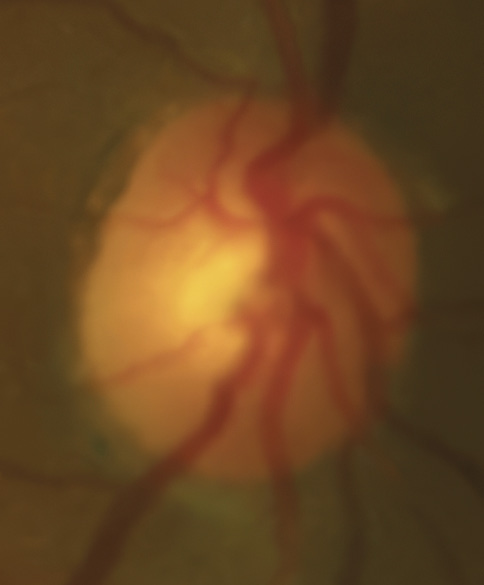

Bild 2: Fall 1 – (a) Sehnervenkopf OD, (b) Sehnervenkopf OS

Her intraocular pressure was measured via Goldmann applanation tonometry (GAT) at 26 mmHg in both eyes at 10:15 am. Intraocular pressure was remeasured via iCare with values of 33 mmHg in each eye. Gonioscopy confirmed open anterior chamber angles and demonstrated no secondary causes for the elevated eye pressure. Assessment of the optic nerve showed an intact and well-perfused neuroretinal rim in both eyes, with normal optic nerve head morphology. Central corneal thickness measurements (CCT) were also measured via optical coherence tomography (OCT) and measured 589 microns OD, 598 microns OS. Baseline optic nerve head OCT, optic disc photos and 24-2 Humphrey Visual Fields were obtained (Figures 1, 2, 3).